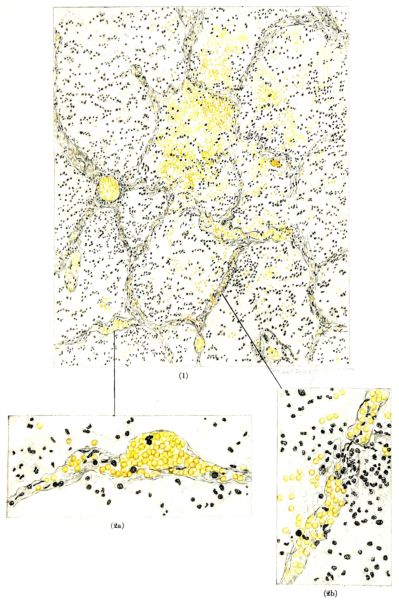

FIG. III. AUTOPSY NO. 90. DRAWING FROM A LESION OF THE TRACHEA (SOMEWHAT OLDER THAN THAT ILLUSTRATED IN FIGURE II). THE MUCOSA IS ENTIRELY LACKING. CONGESTION AND EDEMA ARE THE STRIKING FEATURES IN THE SUBMUCOSA. THE NECROTIZING PROCESS HAS EXTENDED INTO THE MUCUS GLANDS. THIS IS SHOWN IN THE LOWER PICTURE.

FIG. XXVI. AUTOPSY NO. 103. THE LARGER ILLUSTRATION OF AN HEMORRHAGIC ALVEOLAR EXUDATE IS ELABORATED BY TWO HIGHER POWER DRAWINGS. THESE SHOW (1) AN ANEURSYMAL DILATATION OF A CAPILLARY IN THE ALVEOLAR WALL AND (2a) A RUPTURE OF THE CAPILLARY WALL WITH THE ESCAPE OF RED BLOOD CELLS INTO THE ALVEOLUS; (2b) NECROSIS WITH EARLY THROMBOSIS OF THE CAPILLARY IN THE ALVEOLAR WALL.